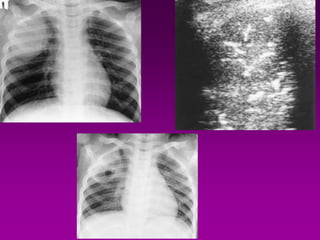

At the bedside, chest radiography remains the reference for lung imaging in

critically ill patients. However, radiographical images are often of

limited quality

• Movements of the chest wall

• Film cassette posterior to the

thorax

• X-ray beam originating anteriorly, at

a shorter distance than

recommended and not tangential to

the diaphragmatic cupola .

Mistaken assessment

of :

c

• Pleural effusion

• Alveolar consolidation

• Alveolar-interstitial

syndrome

c At the bedside,chest radiography remains the reference for lung imaging in critically ill patients. However, radiographical images are often of limited quality • Movements of the chest wall • Film cassette posterior to the thorax • X-ray beam originating anteriorly, at a shorter distance than recommended and not tangential to the diaphragmatic cupola . Mistaken assessment of : c • Pleural effusion • Alveolar consolidation • Alveolar-interstitial syndrome Bedside Chest Radiography in the Critically ill 02 09 2012